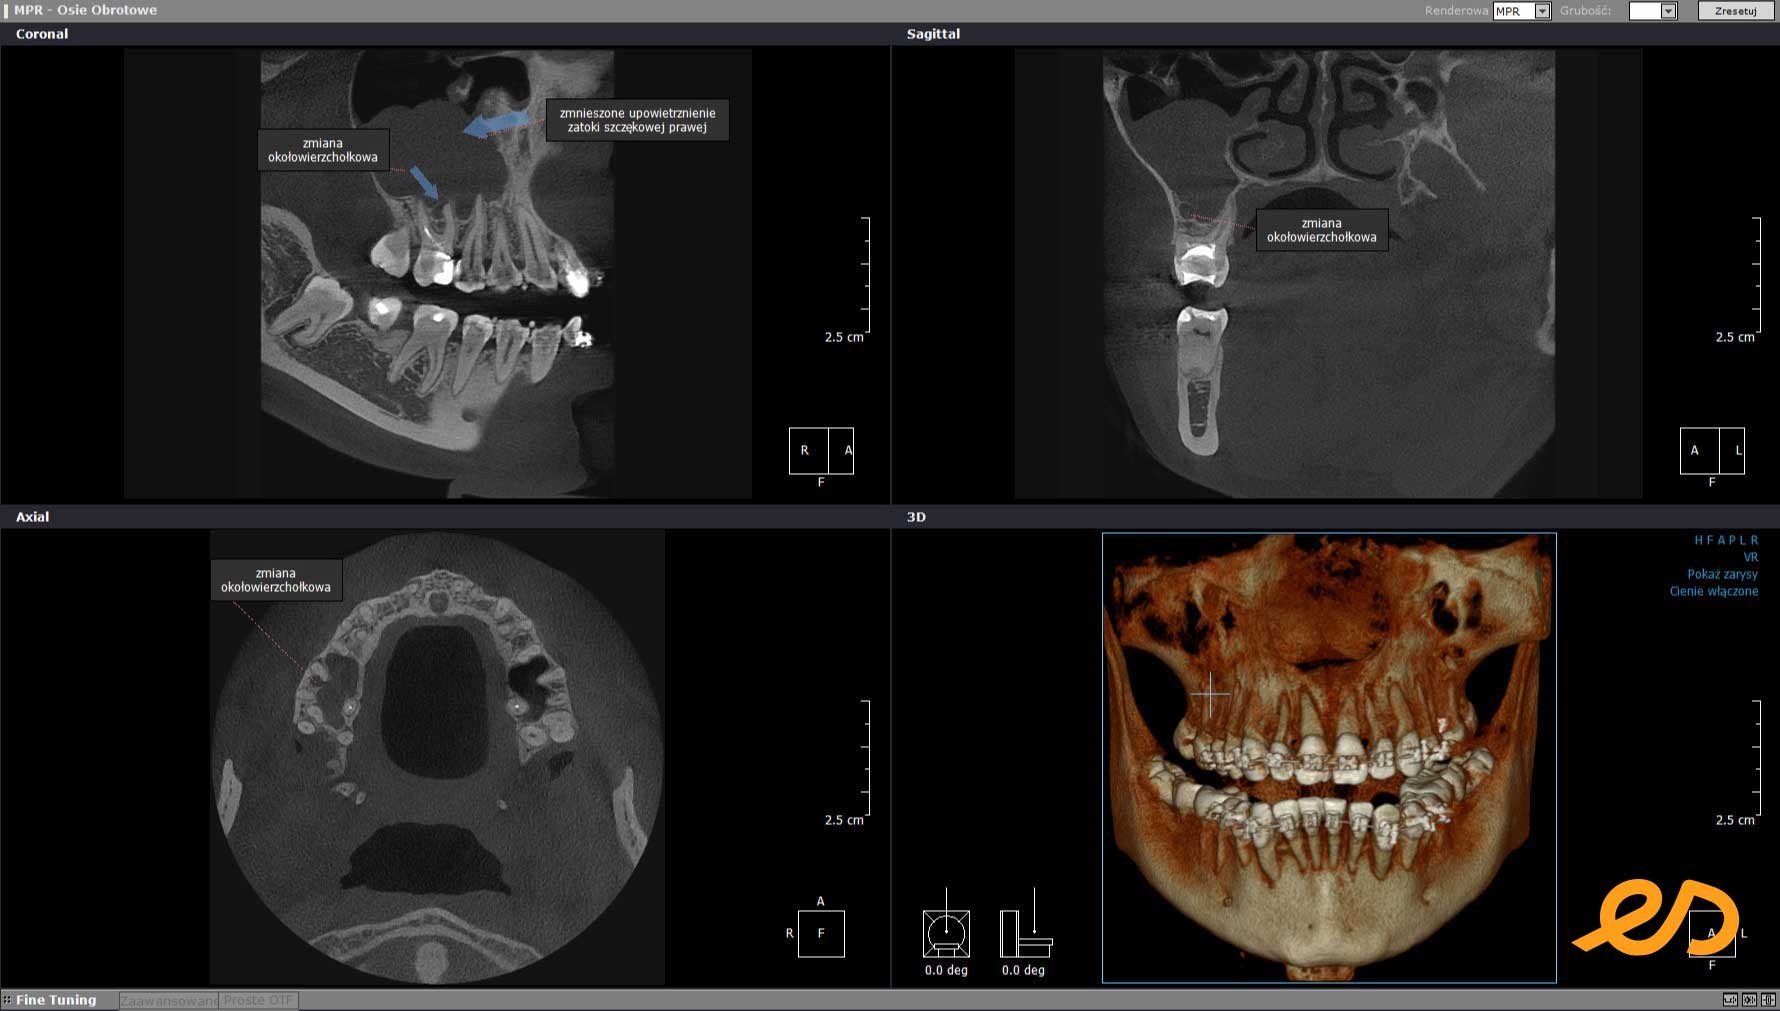

Przykładowo, poniżej badanie TK pacjenta z aparatem ortodontycznym. Pomimo powstających artefaktów, doskonale widzimy stan zębów, wypełnień i okolicznych tkanek. Przy zębie szóstym po prawej stronie w szczęce z niedopełnionym kanałem korzeniowym jest zmiana okołowierzchołkowa. Co więcej widoczne jest zmniejszone upowietrznienie prawej zatoki szczękowej wskazujące na toczący się w niej stan zapalny.

badanie tomograficzme cbct stan zapalny zatoki 1744197277